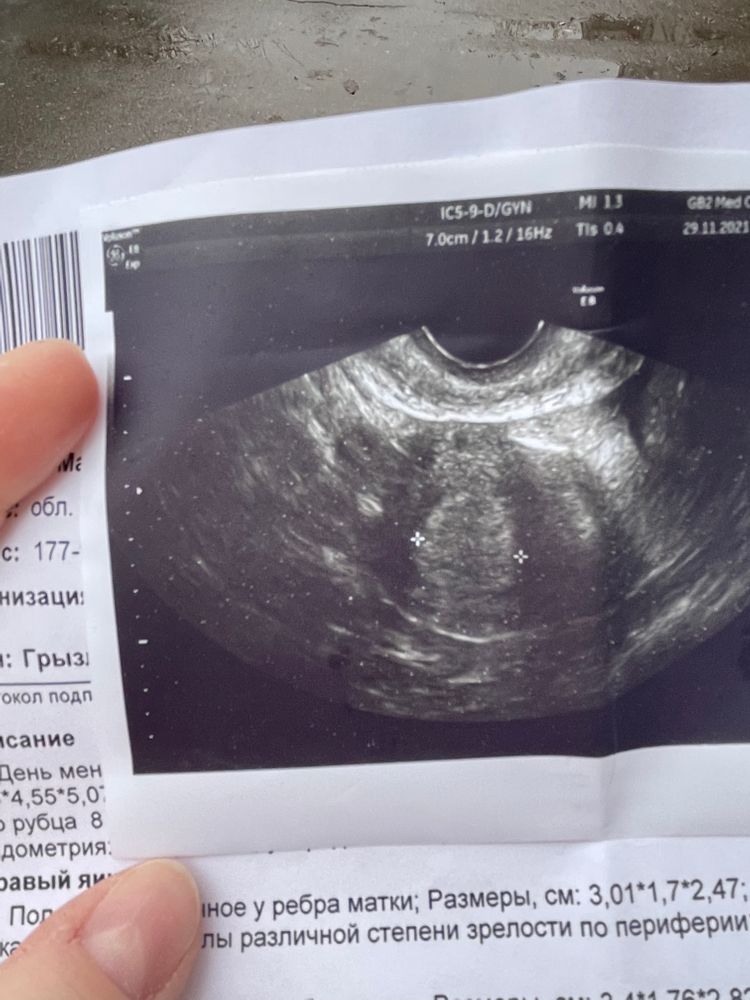

Узи на 18 день цикла ( овуляция) УЗИ , овуляция после перелета (отдыха на море)